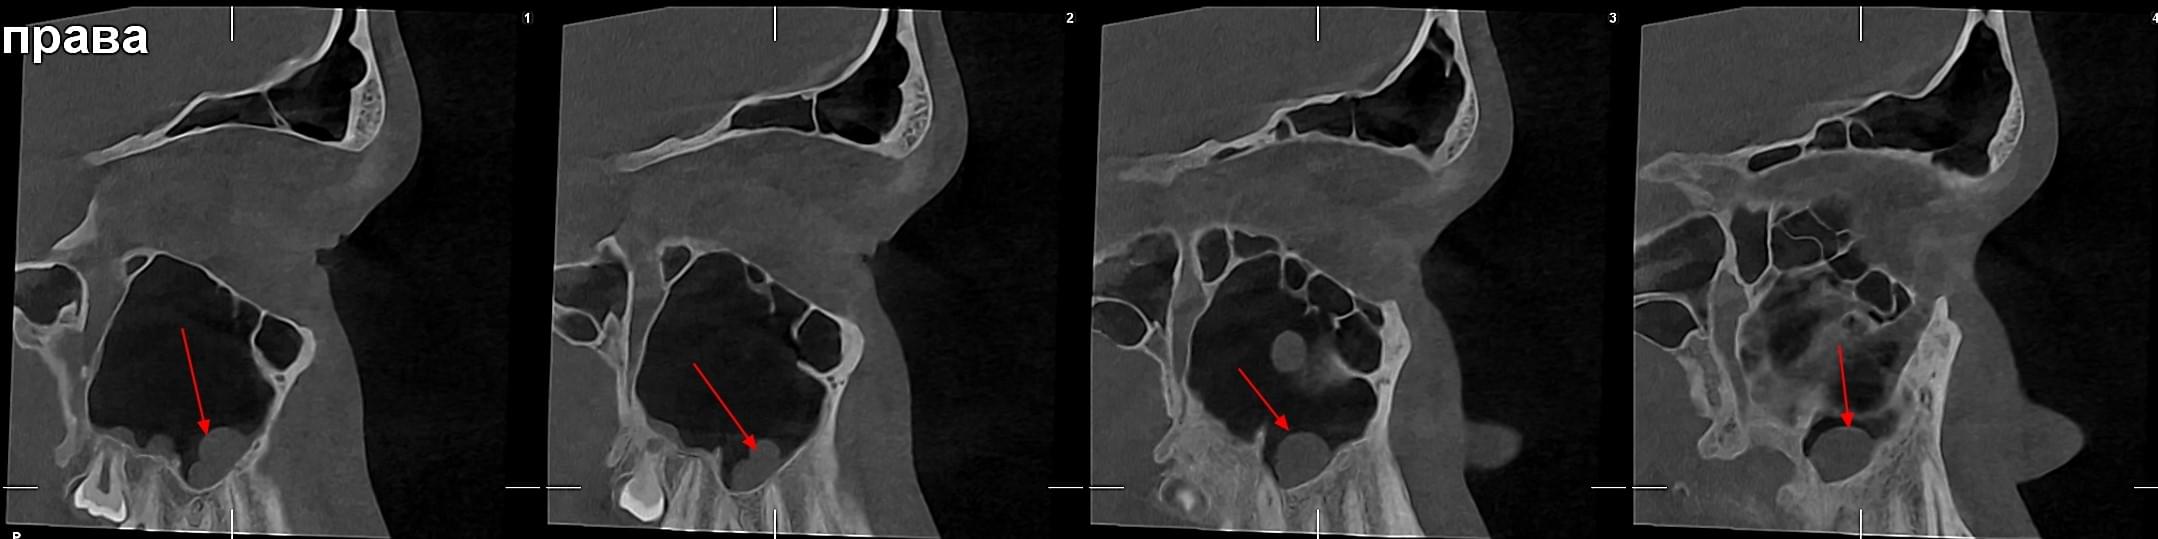

Важливо: Якщо нежить триває понад 2 тижні, з’явилася температура, набряк обличчя чи біль в очах — не відкладайте візит до ЛОРа. Раннє КТ пазух носа дозволяє виявити приховані кісти, поліпи, сторонні тіла або одонтогенний гайморит ще до ускладнень.

КПКТ (конусно-променева комп’ютерна томографія) — це 3D-знімок високої роздільної здатності. На відміну від звичайного рентгену, КТ показує:

КТ дозволяє провести віртуальну операцію: встановити імплант у програмі, виключивши будь-які ризики травмування пацієнта.